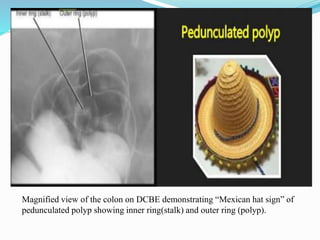

This document discusses colorectal polyps. It defines polyps and describes their types, including neoplastic and non-neoplastic polyps. It discusses adenomatous polyps in depth, noting their malignant potential increases with size over 1cm and villous architecture. Radiological diagnostic methods for polyps including single and double contrast barium enema and CT colonography are explained. The document provides an overview of polyp pathogenesis and genetic syndromes like FAP that increase cancer risk.